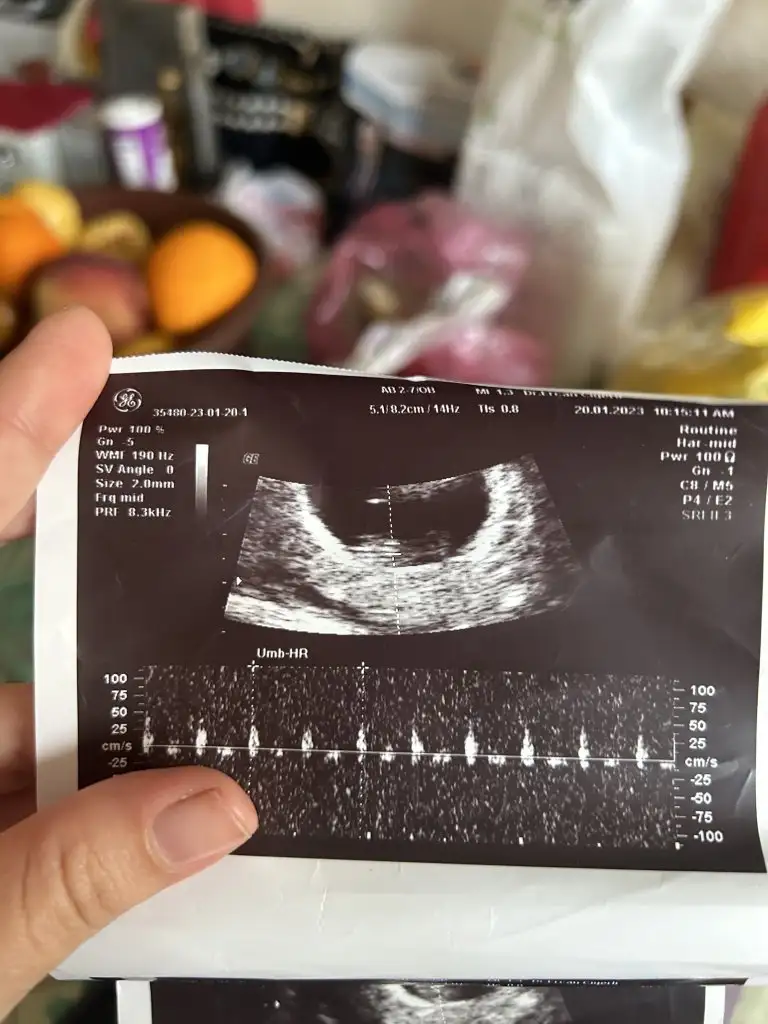

Pekiii bende ne dersin ?

Üstteki 9 haftalik diger ikisi 7 haftalik, ve vaginal ultrason :)